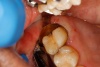

Figure 8A is a radiograph revealing deep root caries previously restored temporarily by a resident at the AEGD Residency Program clinic with glass ionomer utilizing a lateral rather than occlusal approach. After the glass ionomer failed to adhere, another resident again attempted a lateral approach that resulted in the restoration shown in Figure 8B. A third resident had success with an occlusal approach, removing a failed occlusal composite to access the distal  (Figure 9). This attempt was successful both in the preparation of the lesion and in the placement of a dual- cure bulk-fill flowable (Bulk EZ Plus, Zest Dental Solutions; alternatively: HyperFIL®, Parkell; Fill-Up!, Coltene) extruded through a bendable needle (Figure 10). Figure 11 shows the final preparation after tissue removal was accomplished with rotary gingitage; note that this was performed with the rubber dam in place. An air abrasion device (Groman Etchmaster, Groman Dental; alternatively: PrepStart H2O, Zest Dental Solutions; Bioclear Blaster, Bioclear) was used with potassium bicarbonate to remove biofilm prior to acid etching (Figure 12). Phosphoric acid 37% was utilized in a total etch fashion (Fig- ure 13 and Figure 14) for 20 seconds. Figure 15 shows the universal bond (Scotchbond Universal, 3M; alternatively: All-Bond Universal®, BISCO; Prelude One, Danville Materials) with metha- cryloyloxydecyl dihydrogen phosphate (MDP) being scrubbed into the cavity for 20 seconds. After air thinning for 20 seconds, the adhesive was light cured for 40 seconds at 1,200 mw/cm2power density (Figure 16).

Respecting the inverse square law, the resident doubled the light-curing time to ensure good adhesive polymerization in the deep box. To facilitate the matrix band providing deep access  (Paraband, Practicon; alternatively: Greater Curve matrix band; Greater Curve), the clinicians needed to remove the dam. Assurance of a dry field was accomplished by placement of bilateral dry angles that stem saliva flow from Stensen's ducts. A swedopter device was placed under the tongue to suction saliva from the sublingual and submandibular glands. Figure 17 shows the gingival area closure accomplished with the Paraband "Elizabethan collar effect"; no wedging is possible, so this Tofflemire type band provides a tight gingival seal by virtue of the band's unusual geometry. In Figure 18, the comfort of injection of the dual- cured bulk-fill flowable utilizing the bendable 20-gauge needle can be noted; it would not be possible to fill this with a paste-type universal composite. Subsequent to a 90-second self-cure phase during which the surface cannot be disturbed, the resident placed starting pits in the mesial central and distal pit areas with the medium acorn of the Occlusinator PRO bur system (StraussUSA; alternatively: R.A.P.T.O.R. Acorn, Henry Schein) (Fig- ure 19). Figure 20 shows the pits created at uniform depth facilitated by the limit stops on the burs. The acorn now is moved in a pit-to-pit pattern that created the planes that form the triangular and oblique ridges as well as the marginal ridges (Figure 21). After the planes were formed, a X-mas tree-shaped diamond bur was used to refine and prepolish the planes formed by the acorn (Figure 22). Refinements such as secondary anatomy can be placed using the mini-acorn (Figure 23). Figure 24 shows a Brownie polisher reshaped to a straight-sided X-mas tree bur that is used to polish the planes, pits, and ridges. In Figure 25, a Greenie polisher is shown that also has been reshaped to be a straight-sided X-mas tree polisher. Both are used at 50,000 to 100,000 rpm and with a copious water spray. Final polish is accomplished with a latch bristle brush coated with TopDotz polishers (Dental Ventures of America; alternatively: Shammy Bright Composite Polishing Paste, Kerr Dental) (Figure 26). As shown in Figure 27, the pure diamond comes in pellet form to facilitate good asepsis. The last polish is applied with a dry latch-type cotton buff (Figure 28). In Figure 29, note the anatomy formed by this technique. It is apparent that this resident accomplished a more than satisfactory result, as evidenced by the post-treatment radiograph (Figure 11).

Fig 15. Universal bond is scrubbed into dentin for 20 seconds, applied to the enamel, and air-thinned.

Figure 15

Fig 16. Adhesive was light-cured for 40 seconds due to the depth of the box preparation.

Figure 16